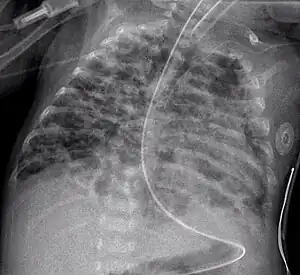

A chest radiograph showing bronchopulmonary dysplasia.